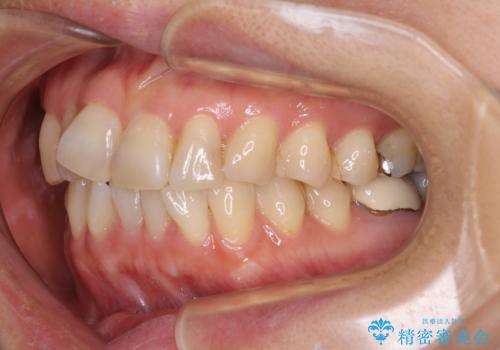

- 矯正装置

- 審美装置

- 前歯のデコボコを気にして来院された患者様です。

舌突出癖により、上下前歯がなかなか接触せずに治療期間を要しましたが、舌のトレーニングにより無事に治療を終えることができました。